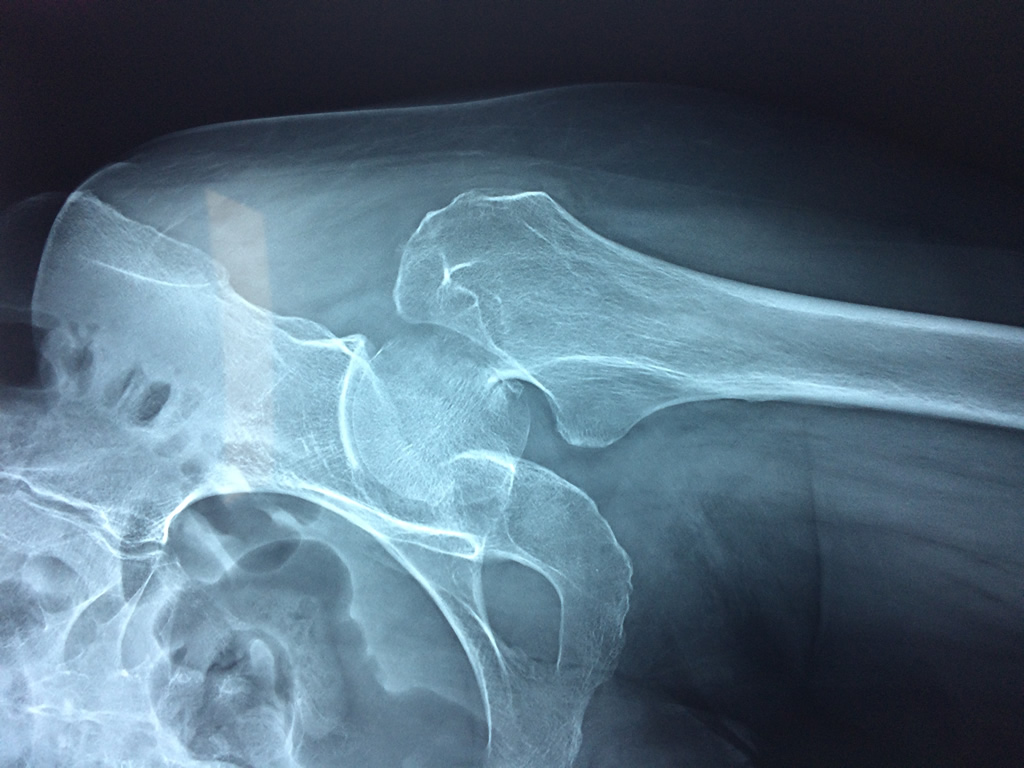

Cirugías de Húmero - Cadera

La cirugía de fractura de cadera se realiza para reparar una ruptura en la parte superior del hueso del muslo. Este hueso se denomina fémur.

Es parte de la articulación coxofemoral. Si una fractura de cadera no recibe tratamiento, es posible que deba permanecer en una silla o en la cama.